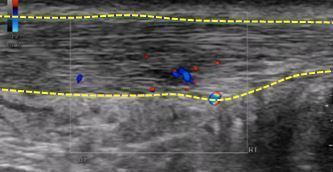

また、超音波診断機器を使って患部に炎症や腫れが起きているかを診断し、アキレス腱炎か確定診断を行っていきます。

レントゲンでは、特に異常所見はない場合でも、超音波検査ではレントゲンでは見ることができないアキレス腱の状態を評価することが可能です。上の写真では右側のアキレス腱の下が左側と比較して黒くぼやけていることが分かります。

アキレス腱の血流を診てみます。

赤と青の色が出ています。これは組織修復のために血管が集まっていることを示します。

血流が多いほど、痛みは強くなっています。

これらの画像所見などから、アキレス腱炎と診断していきます。